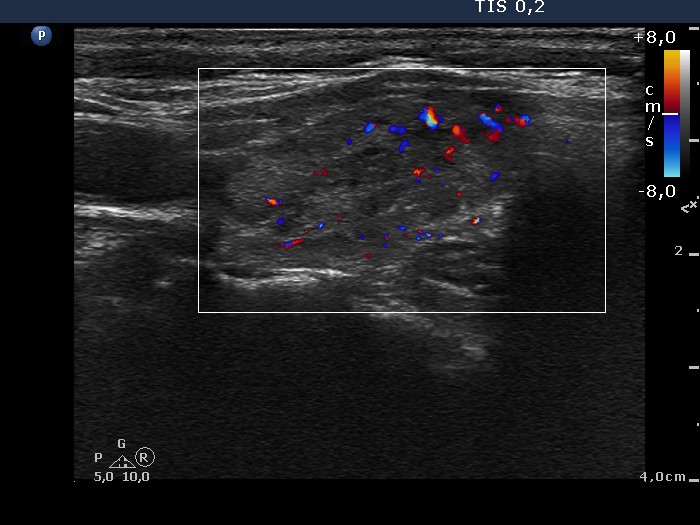

Chronic lymphocytic thyroiditis - Case 31.

One year later in euthyroid state (ultrasonographic picture 6)

Left lobe, horizontal scan, color Doppler mode. The vascularization is average.